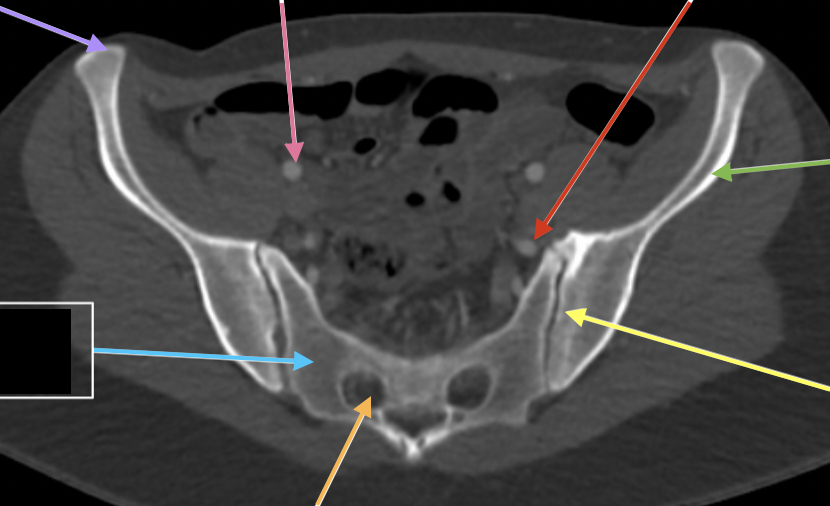

v iliaca communis dx

grön

a iliaca communis dx

orange

a iliaca communis sin

gul

v iliaca communis sin

röd

v iliaca interna dx

a iliaca interna dx

rosa

v iliaca externa dx

ljusblå

a iliaca externa dx

a iliaca externa sin

a iliaca interna sin

v iliaca externa sin

brun

v iliaca interna sin

mörkblå

spina iliaca posterior superior

blå

m psoas major dx

promontorium

m iliacus sin

foramina sacralis

os sacrum

spina iliaca anterior superior

lila

os ilium

art sacroiliaca

a iliaca externa